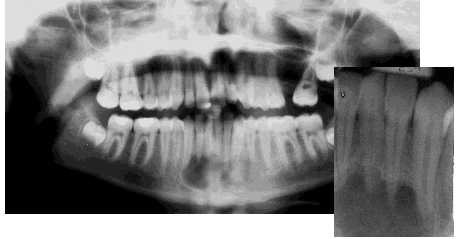

What is an odontogenic keratocyst?

What is Gorlin-Goltz syndrome?

Multiple basal cell carcinomas of the skin

Odontogenic keratocysts: Seen in 75% of patients and is the most common finding. There are usually multiple lesions found in the mandible. They occur at a young age (19 yrs average).

Rib and vertebrae anomalies

Intracranial calcification

Skeletal abnormalities: bifid ribs, kyphoscoliosis, early calcification of falx cerebri

Distinct faces: frontal and temporopariental bossing, hypertelorism, and mandibular prognathism